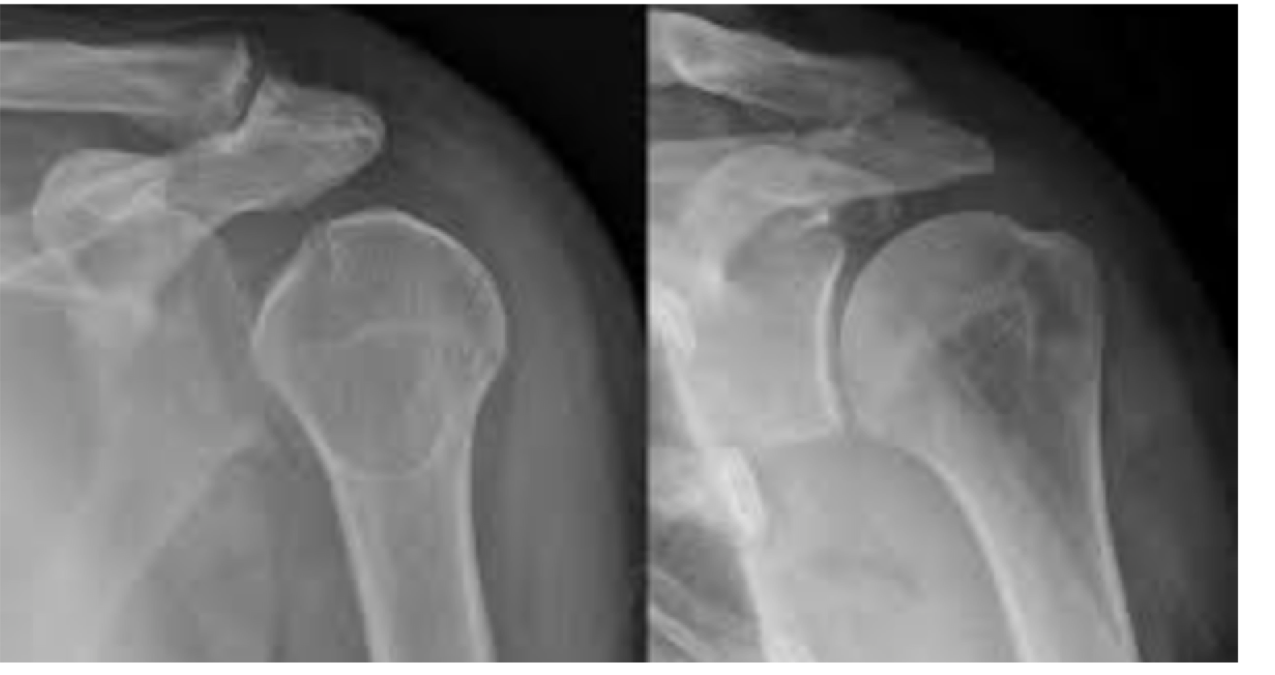

What does this radiograph show?

A posterior dislocation of shoulder